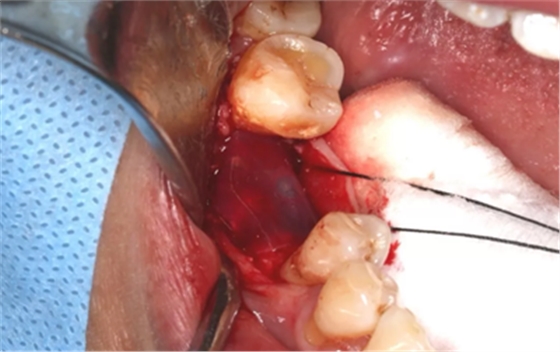

无张力间断缝合切口。

(摄于2017年8月10日)